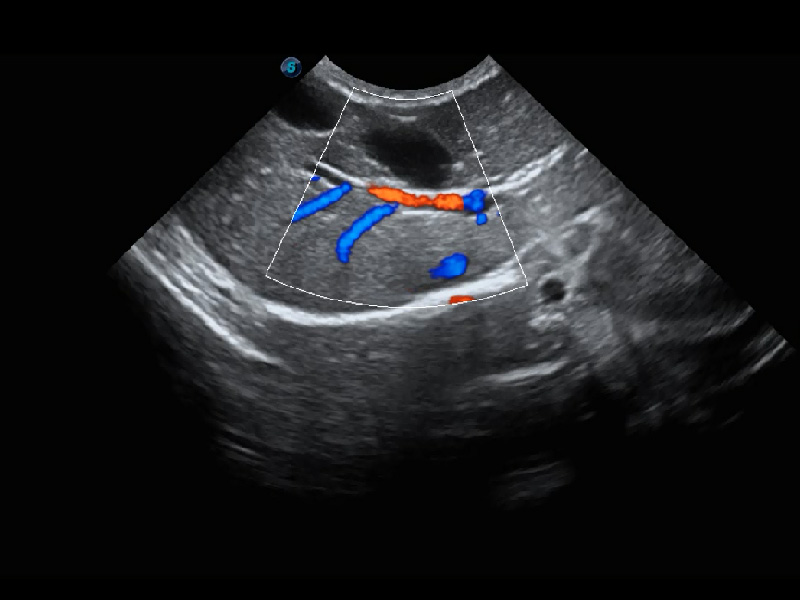

ProPet 60 作为一款高端台式动物超声设备,为动物医生的日常诊断提供了一系列贴合动物临床需求、解决临床实际问题的高级成像功能。凭借全系列高清探头,满足医生对腹部、心脏、生殖、浅表、肌骨等成像的所有需求,切实帮助您提升检查效率,提高诊断信心。

动物是人类最亲密的朋友和最值得信赖的伙伴。玖鼎集团也一直致力于探索动物专用的超声影像解决方案。 全新推出的ProPet系列,是玖鼎集团在动物超声影像智能化、专业化、精准化的一次跨越式革新。动物不能用言语来表述自己的不适,通过超声影像,ProPet系列搭建了动物医生与不同物种沟通的“桥梁”,为动物医生注入了“治愈之力”。